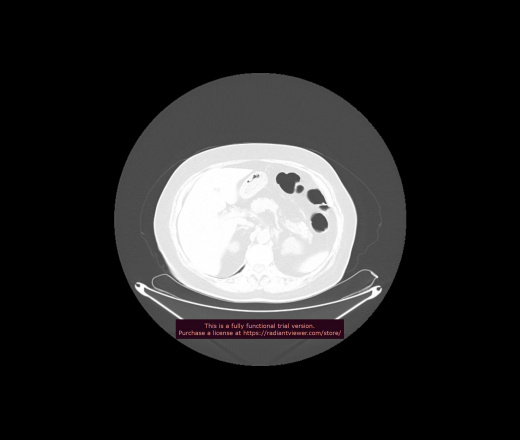

Уважаемые коллеги, если имеется интерес, сможете ли Вы спрогнозировать дальнейшее +-одинаковое течение процесса у 4 данных разных пациентов? Зацепиться где-то можно очень просто, где-то нельзя.